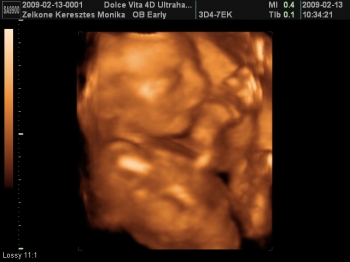

Az 1. Női Klinikán voltam szívuh-n.